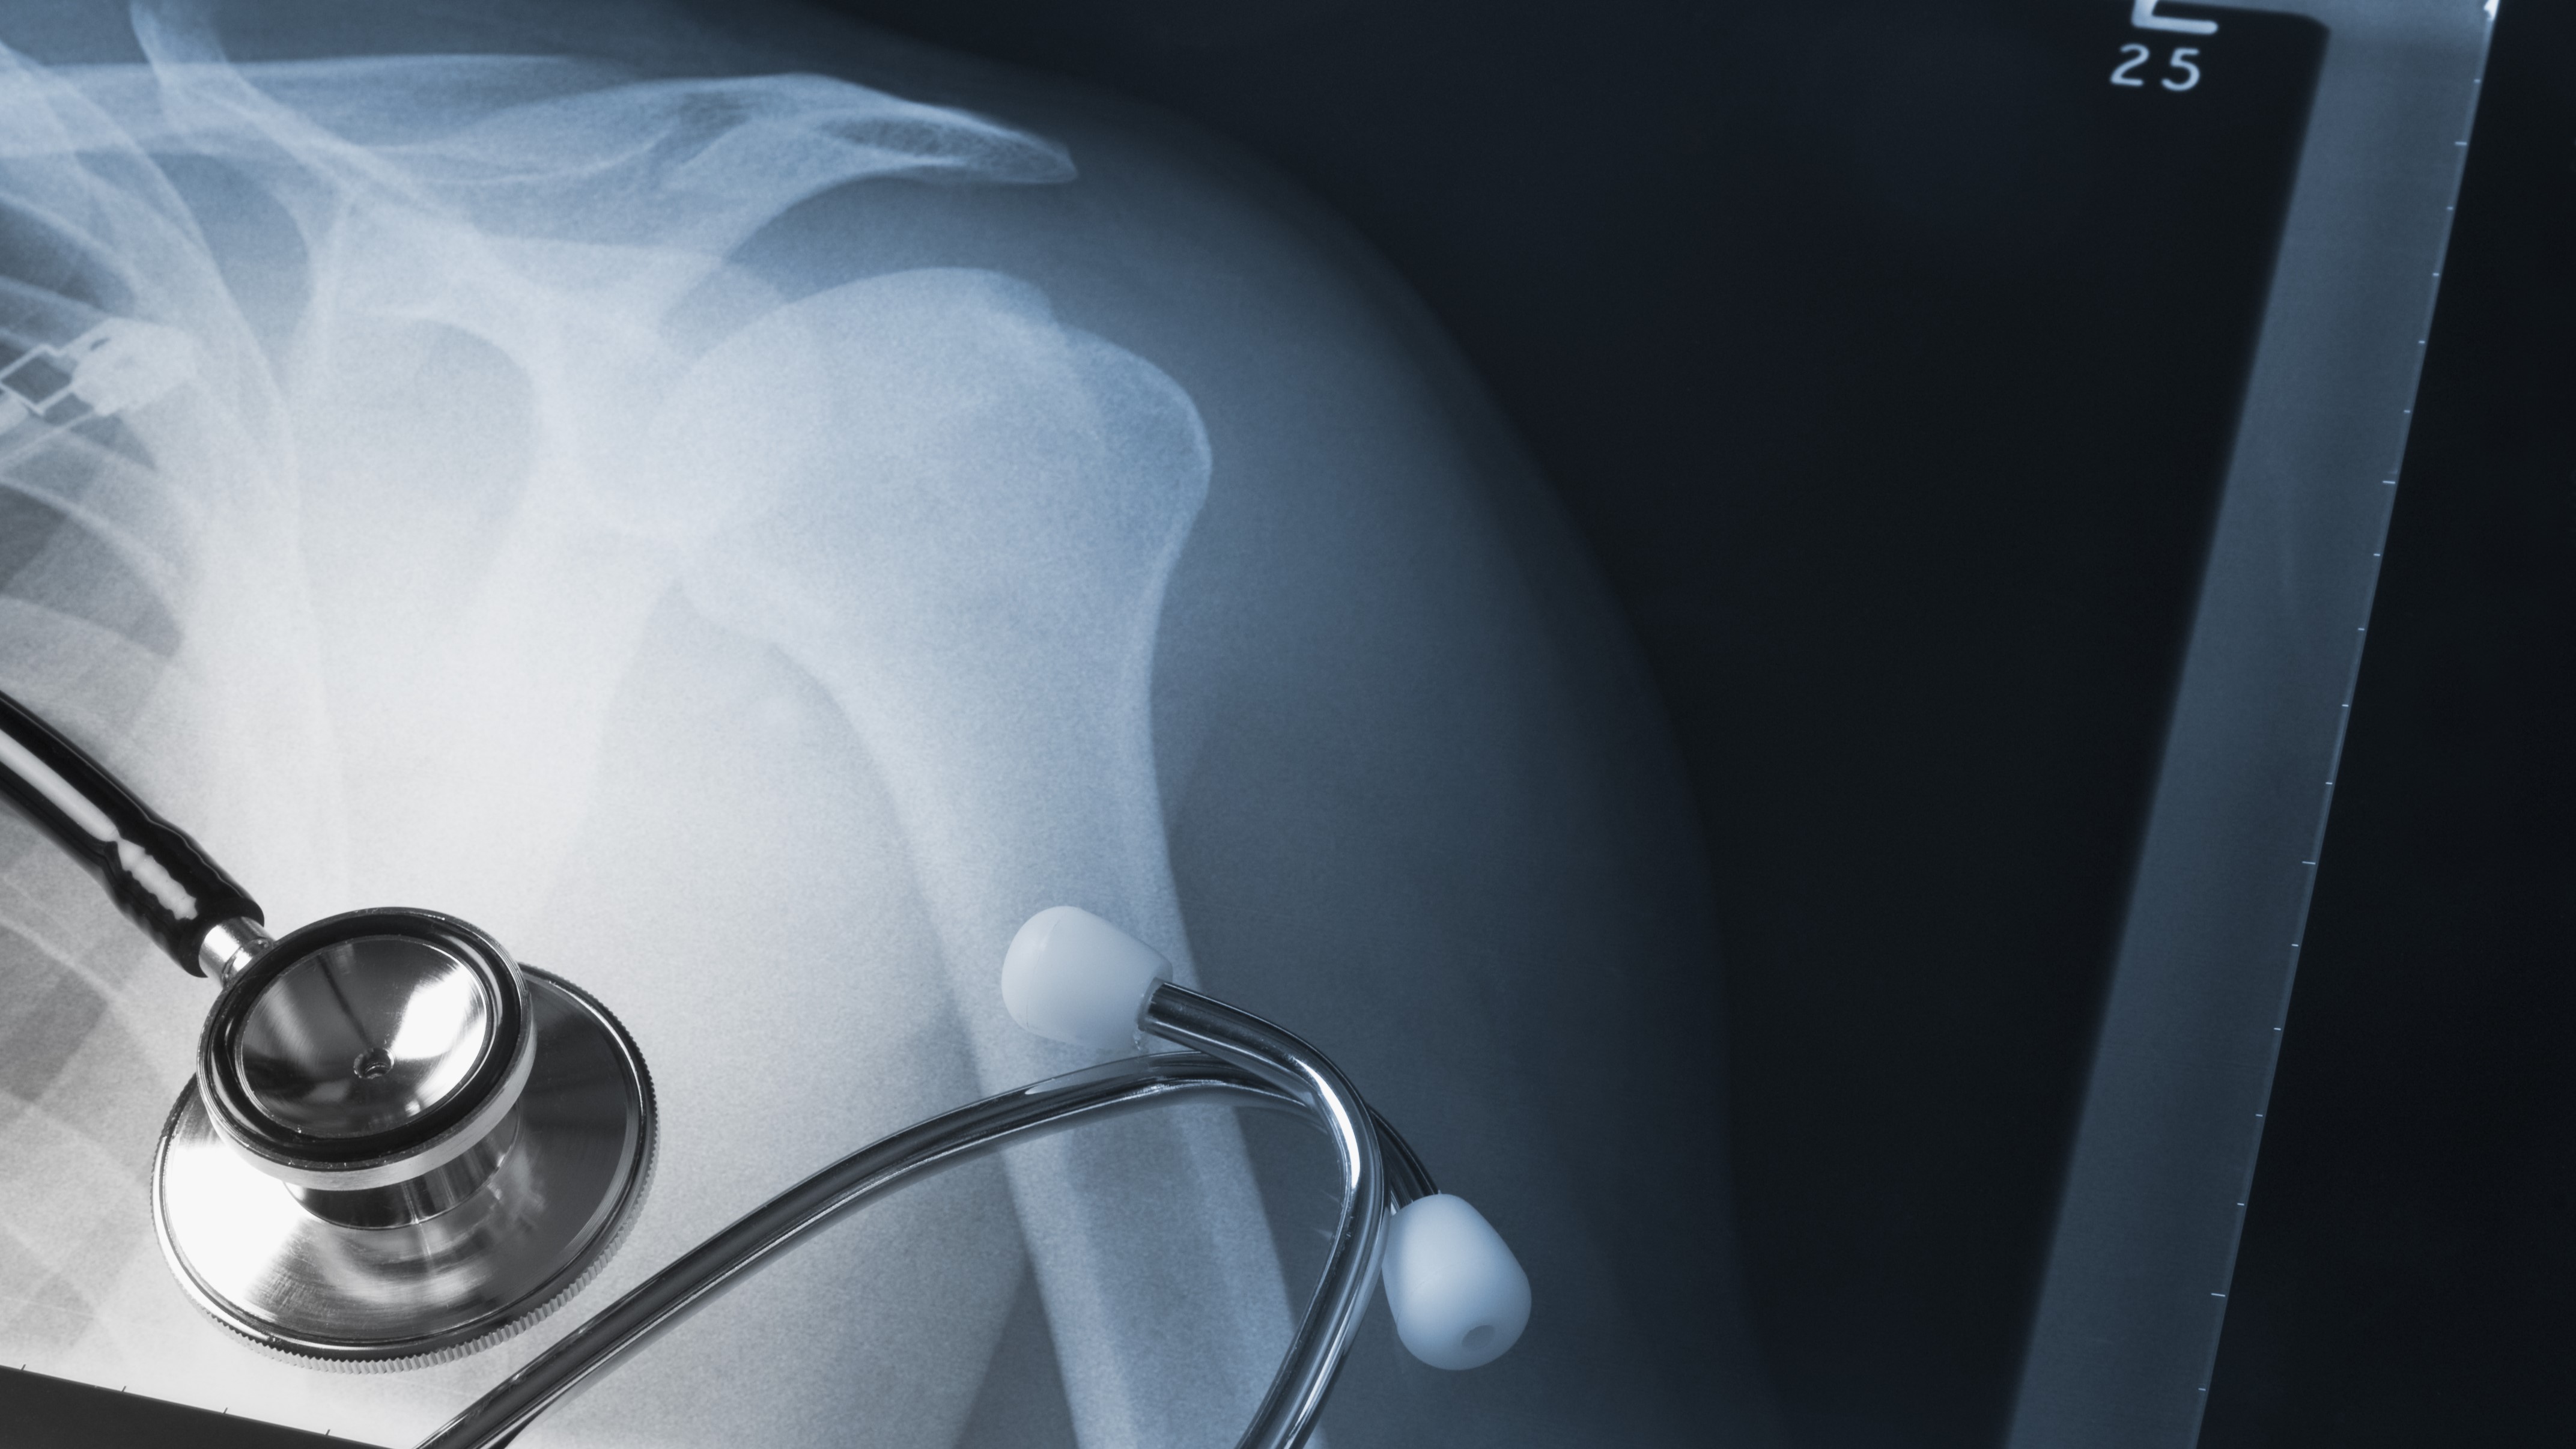

"Really nasty": The causes and consequences of dislocated shoulders

Photo / Getty

• An Xray to make sure it is not broken.